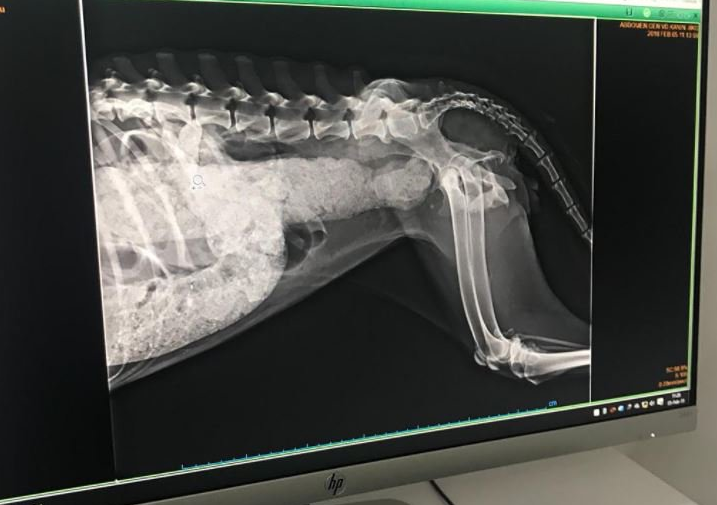

Çekilen röntgenler sonucunda korkunç durum ortaya çıktı. Köpeğin makatından silikon sıkıldığı belirlendi. Ameliyata alınan köpek tüm müdahalelere rağmen kurtarılamadı.

Coffee 2 haftadır @eceaykultas ve @watdirivizzik in peşinde olduğu bir köpekti. İskeleti çıkmış, 10 adımda bir kaka yapmaya çalışıp yapamayan genç dişi bir köpek. Yaptığı kaka da zift gibi, kanama var. Yakalanmasına yardım eden işçiler tinercilerin silikon sıktığını söyledi! Bugün çekilen röntgende bağırsakların komple dolu olduğu görüldü. Röntgeni sola kaydırarak görebilirsiniz. Doktorumuz elle muayene etti, içerisi taş gibi olmuş! Ne yemek yiyebiliyor, ne kaka yapabiliyor. Yaşaması resmen mucize!! Bu akşam operasyona girecek, kalın bağırsaktan bu illet nasıl temizlenir bilmiyoruz dua edin. Karaköy’deki köpekler büyük tehlike altında, lütfen artık bir şeyler yapın. Coffee’de çok ciddi bir enfeksiyon var aynı zamanda. Şu anda toksoplazma tedavisi görüyor, tedaviye verdiği cevaba göre daha güzel gelişmeler aktaracağız inşallah size. Onun için öncelikle dua edin. Tedavisi için de desteğe ihtiyacımız var. Umarım iyileştiği ve yuva bulduğu günler bir an önce gelir. Lütfen paylaşın!